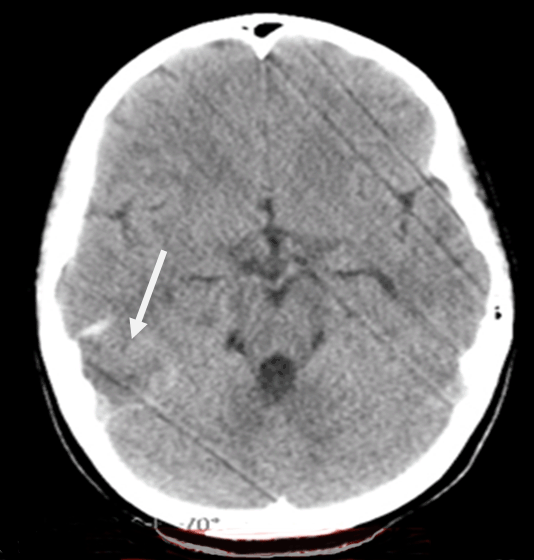

An 11-year-old girl presented with headache, vomiting, dizziness, dysphasia and gaze dedication for a few seconds. The initial computed tomography (CT) scan revealed intracerebral hematoma (ICH) in the right parieto-occipital region with perilesional edema (Figure 1).

Figure 1: The initial computed tomography scan, after the ictus. Arrow depicts the area of ischemic stroke (hypodense), with a surrounding area of hemorrhagic transformation.